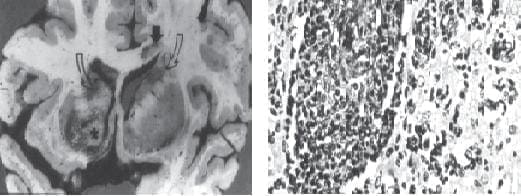

Aunque ya se vienen informando diferentes tipos histológicos de neoplasias intra y extra craneanas aso ciadas a la infección por VIH, solamente el linfoma primario del neuroeje comienza a ganar una signifi – cancia esta dística; 6 casos entre 400 autopsias de SIDA- (Los Angeles County General Hospital – Roy H.Rhodes); otras series informan hasta 3% (fi g 5 a, b y c y fi g 6 a y b).

Figura 5. Comparando a) linfoma primario con b) toxoplasmosis se nota tanta semejanza que resulta comprensible la difi cultad o hasta imposibilidad que la interpretación de las imágenes ofrece (cortesía de JH.García) como ejemplo veáse c) y escoja su diagnóstico.

Figura 6. a) En este paciente con SIDA pudo comprobarse la asociación de linfoma primario con toxoplasmosis (cortesía de JH García. b) Linfoma primario cerebral – 250x aprox. Primer caso de este tumor comprobado en un paciente con SIDA en 1983 en la Fundación Santa fe por uno de nosotros, GT-.